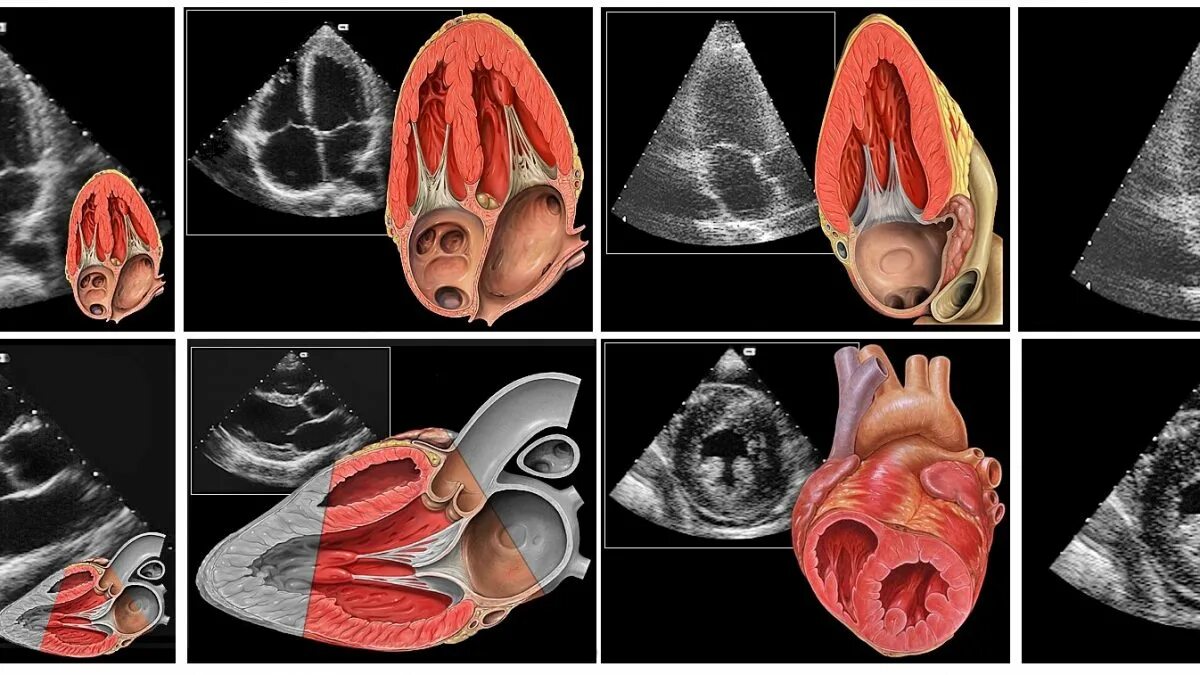

Эхокардиография как делают женщинам